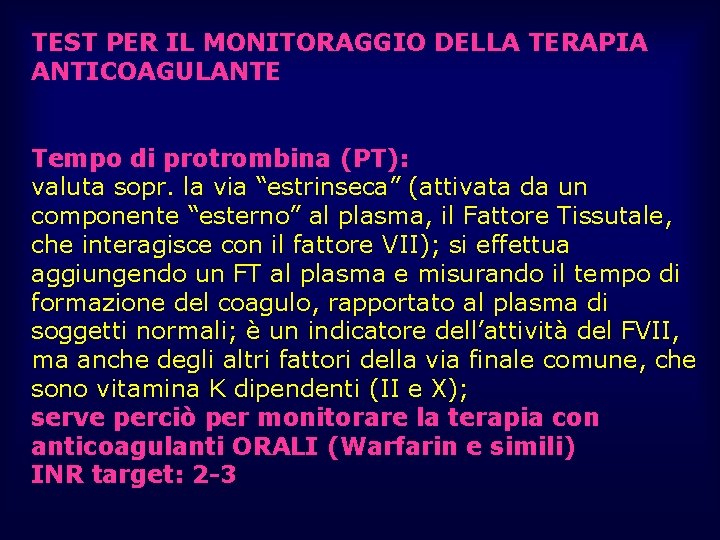

TEST PER IL MONITORAGGIO DELLA TERAPIA ANTICOAGULANTE Tempo di protrombina (PT): valuta sopr. la via “estrinseca” (attivata da un componente “esterno” al plasma, il Fattore Tissutale, che interagisce con il fattore VII); si effettua aggiungendo un FT al plasma e misurando il tempo di formazione del coagulo, rapportato al plasma di soggetti normali; è un indicatore dell’attività del FVII, ma anche degli altri fattori della via finale comune, che sono vitamina K dipendenti (II e X); serve perciò per monitorare la terapia con anticoagulanti ORALI (Warfarin e simili) INR target: 2 -3